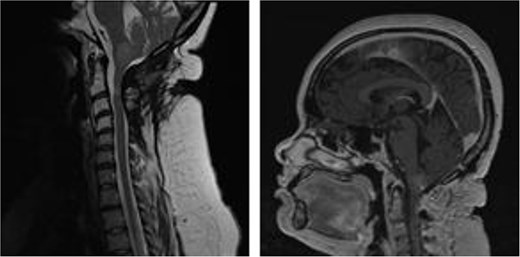

Magnetic resonance imaging brain with gadolinium demonstrated a ring enhancing cystic lesion in the posterior fossa, with solid enhancing extension into the spinal canal down to the C3 level (Fig. 1). The radiological appearance was consistent with an ependymoma.

MRI brain demonstrating cystic posterior fossa mass, with solid component extending past the foramen magnum, down to the level of C3, on sagittal and axial views, respectively.